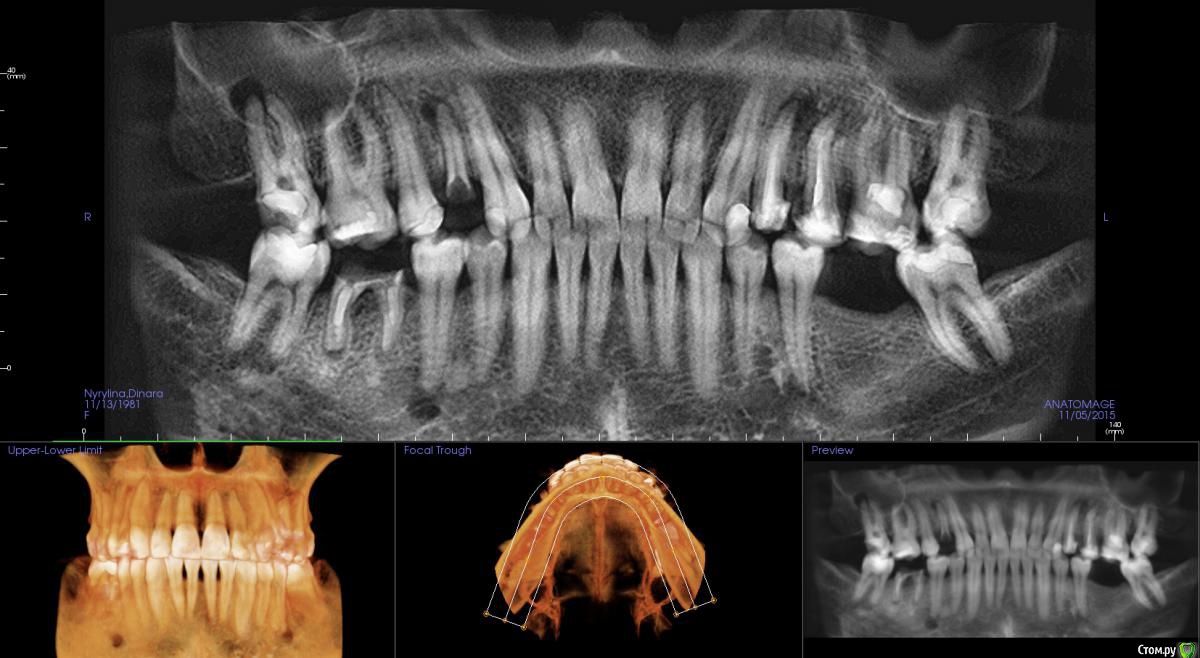

kamranchick Опубликовано 5 ноября, 2015 Поделиться Опубликовано 5 ноября, 2015 Добрый день уважаемые форумчане)Хочу посоветоваться с Вами.Пациент обратился по поводу 14 зуба, хочет удалить и поставить имплантатаБыло предложено идти но одномоментную имплантацию.Вопрос - есть ли противопоказание в данном случае? нужно ли аугментация?Я рассматриваю варианты с устновкой имплантата ALpha Bio SPI 3.3 -13мм, и установка формика с шашлычком(так как бугры хорошие), при условии хорошего торкаВаши советы... Ссылка на комментарий

Doctorstomlis Опубликовано 5 ноября, 2015 Поделиться Опубликовано 5 ноября, 2015 Добрый день уважаемые форумчане)Хочу посоветоваться с Вами.Пациент обратился по поводу 14 зуба, хочет удалить и поставить имплантатаБыло предложено идти но одномоментную имплантацию.Вопрос - есть ли противопоказание в данном случае? нужно ли аугментация?Я рассматриваю варианты с устновкой имплантата ALpha Bio SPI 3.3 -13мм, и установка формика с шашлычком(так как бугры хорошие), при условии хорошего торкаВаши советы...А почему бы не попробовать пролечить?Найти грамотного терапевта.Сейчас такое можно лечить на ура.Правда я не видела фото во рту. Ссылка на комментарий

ПалСаныч Опубликовано 8 ноября, 2015 Поделиться Опубликовано 8 ноября, 2015 Отличный пример под мой вопрос: в области верхушки очаг хронического воспаления, если гранулема уйдет целиком, то ладно; а если удалить корень без нее, то хоть как там кюретируй, нотгарантии что все выудил нет, да и лунка в апикальной трети сплющена. Ставить можно? Или риск нагноения высок? Ссылка на комментарий

Astronaft Опубликовано 8 ноября, 2015 Поделиться Опубликовано 8 ноября, 2015 если гранулема уйдет целиком, то ладно; а если удалить корень без нее.Ставить можно? Или риск нагноения высок?Гранулему легко будет выскоблить. Другое дело неоформленные грануляции. Их мне кажется нереально удалить полностью. Давно какую-то книгу читал, там автор рекомендовал от 6 мес срок, что бы дать грануляциям разрешиться самостоютельно. Описывал там и лазер и медикаментозную обработку, но как предпочтительный способ рекомендовал - дать организму самому справиться. Риск нагноения не велик, но возможно получить долгоиграющую, размытую симптоматику. Грануляции могут своей жизнью в глубине. А доктор думает, что пациент ку-ку... Общался с группой людей которые вообще считают, что перио.связку, грануляции и т.д надо довольно агрессивно убирать ( и не кюретой, а бором или пьезо).Много раз видел на КТ очертания лунок 20-30-40 летней давности. ПалСаныч, я как книгу прочитал, так в грануляции и не имплантирую, всегда жду 6 мес. 1 1 Ссылка на комментарий

kriokov Опубликовано 8 ноября, 2015 Поделиться Опубликовано 8 ноября, 2015 Давно какую-то книгу читал, там автор рекомендовал от 6 мес срок, что бы дать грануляциям разрешиться самостоютельно. про пародонтит попадалось, что и через 6 мес в костной ткани после удаления присутствует остаточная микробная флора. Отличный пример под мой вопрос: в области верхушки очаг хронического воспаления, если гранулема уйдет целиком, то ладно; а если удалить корень без нее, то хоть как там кюретируй, нотгарантии что все выудил нет, да и лунка в апикальной трети сплющена. Ставить можно? Или риск нагноения высок?ПалСаныч, только из собственного опыта- если при ревизии после удаления следов гноя нет, ставлю. Если получаю гной при ревизии, то нет. Щель ауто пакую, за него и боюсь. Про сужение лунки в апикальной трети, не совсем понял, но думаю , там же верхушка болта все равно чуть небнее пойдет. Ссылка на комментарий